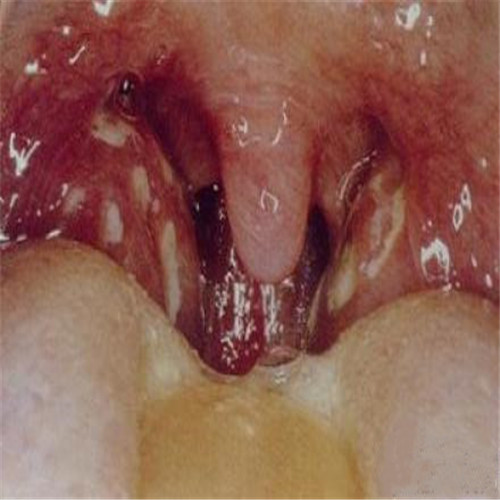

呼吸道感染一側潰爛

呼吸道感染兩側發炎